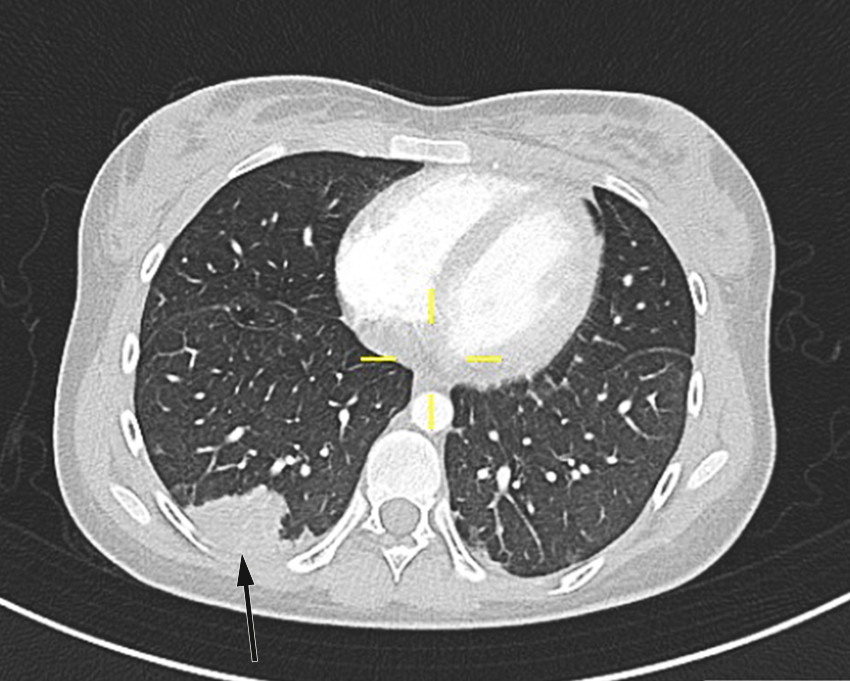

Pasienten fikk smerter i venstre del av toraks på dag 2. CT toraks og abdomen viste funn forenlig med septiske embolier i begge lunger og mulig infarktkomponent i høyre underlapp (figur 2, figur 3). I tillegg var det lett forstørret lever og milt, periportalt ødem samt små mengder fri væske i bekkenet (mulig fysiologisk). Det var også beskrevet mistanke om tromber i vena subclavia og vena axillaris på høyre side. Dag 3 så man oppvekst av penicillinfølsomme Streptococcus anginosus i blodkultur. Serologiske prøver viste svakt positivt Epstein-Barr-virus (EBV)-viralt kapsidantigen (VCA)-IgG, svakt positivt EBV-VCA-IgM og negativt EBV-EBNA-IgG. Intravenøst benzylpenicillin og klindamycin samt antikoagulasjonsbehandling med lavmolekylært heparin (enoksaparin) ble kontinuert.